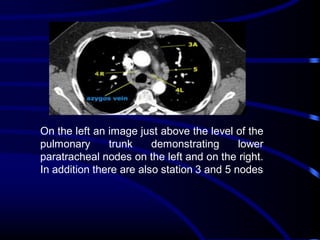

On the left an image just above the level of the

pulmonary

trunk

demonstrating

lower

paratracheal nodes on the left and on the right.

In addition there are also station 3 and 5 nodes